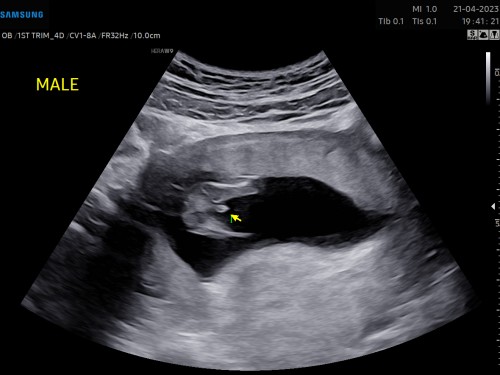

ซาวด์ตอน 13 วีค หมอบอกผู้ชาย 90% แม่ๆคิดว่ามันจะกลายมั้ยคะ หรือมันชัวร์แล้ว เพราะมันชัดมากๆ

อันนี้ซาวด์ตอน19w. หมอบอกเป็นผช. แต่ไปดูในติ๊กต๊อกมาเหมือนกัน กลัวจะกลายเหมือนเค๊า 😂 แต่อิแม่ก็ว่าถ้าไม่ใช่มันจะชัดขนาดนี้เลยรึ

บ้านนี้ก็เห็นจูจู้แบบนี้ตอน13วีค หมอบอก90% เหมือนกันเลย ตอนนี้18วีคหมอคอนเฟิร์ม100% เลยค่ะ🤣

บ้านนี้ก็รู้เพศตอน13wค่ะ จู๋โผล่แบบนี้เลย ตอนนี้น้องคลอดได้3เดือนแล้วค่ะ 🥰

ชัดแล้วค่าแม่ ตอนหนู13weekก็แบบนี้ค่ะ ตอนนี้21weekหมอบอกชาย100%